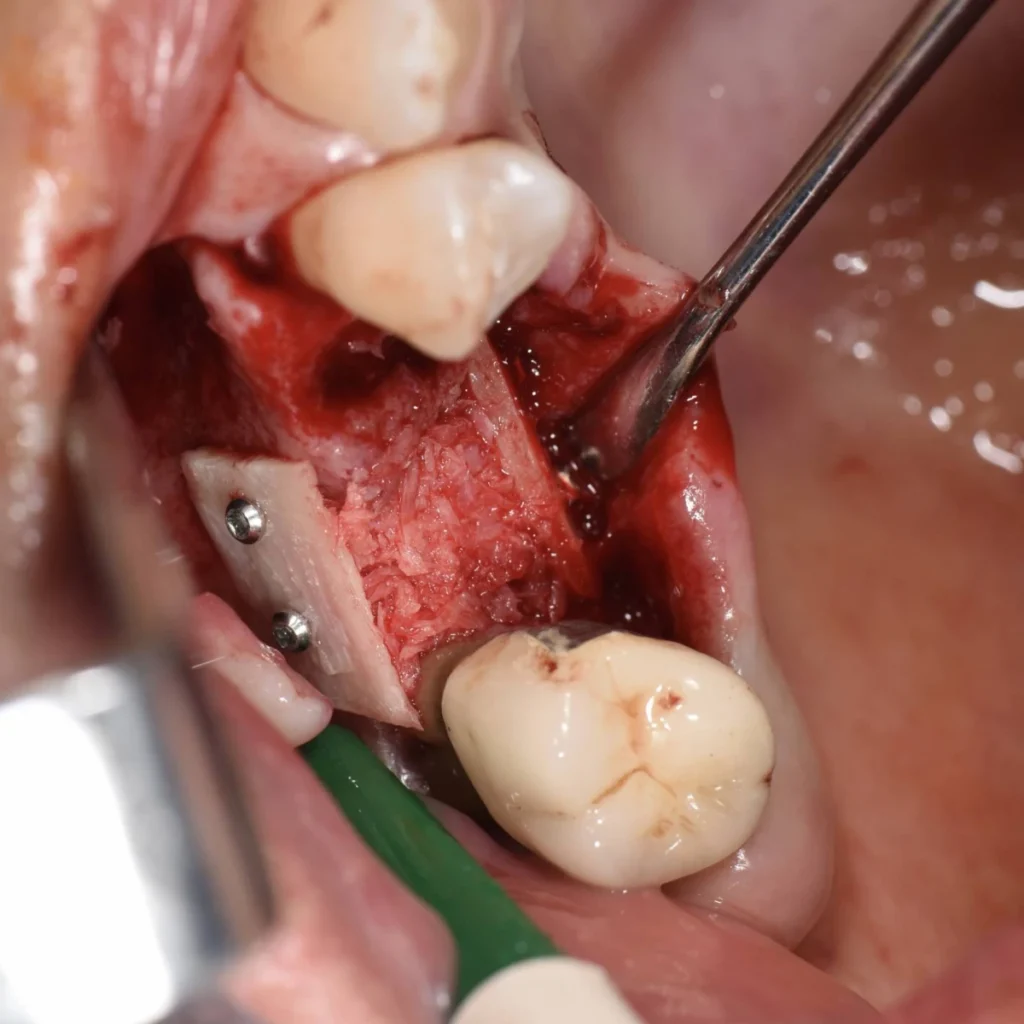

- Il s’agit de prélever un greffon osseux dans la zone postérieure de la machoire inférieure de la patiente. Ce greffon est ensuite modelé et transfixé avec des vis au niveau du site à traiter.

- La gencive est ensuite refermée avec des sutures.